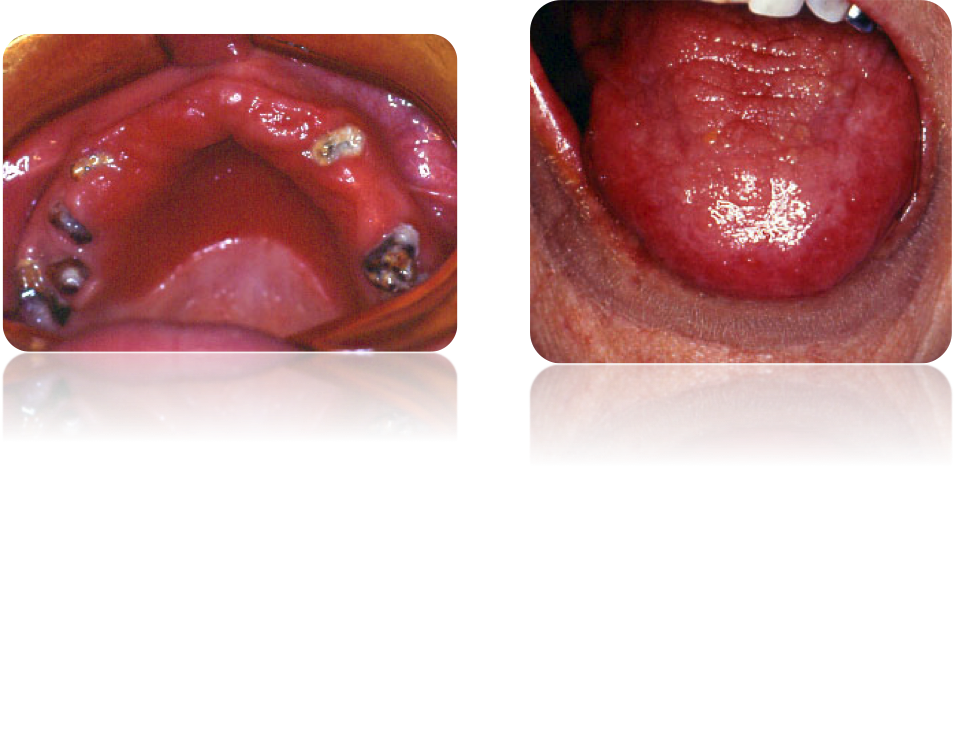

Candidose evocatrice du VIH

Sarcome de Kaposi evocateur du VIH